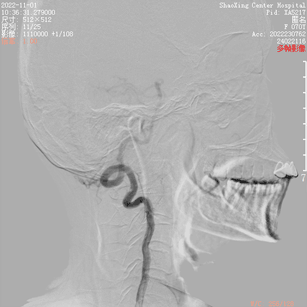

患者入院2月前无明显诱因下出现左侧耳鸣,呈吹风样,持续性,节律与脉搏一致,无明显加重缓解因素,声音与头位或体位无关,无头痛头晕,无恶心呕吐,当时就诊当地医院对症处理,无好转。入院1天前就诊于当地医院查MRA(图1)及脑血管造影(图2)提示“左侧颈外动脉造影见咽升动脉供血通过岩上窦、海绵间窦向双侧颈内动脉引流的动静脉瘘。左侧椎动脉造影显示左侧椎动脉开口无狭窄,椎动脉硬膜支供血向同侧椎旁静脉引流的瘘形成”,现为进一步治疗来院。

根据病史及当地医院辅助检查,诊断后颅窝硬脑膜动静脉瘘明确。分析当地医院MRA及血管造影结果,大致可判断该患者瘘口位于左侧舌下神经管或髁前汇区。详细读片可见左侧颈外动脉造影及椎动脉造影所示引流模式相同。入院后完善脑血管造影检查,并应用双容积影像后处理技术进行三维重建(图3)。便于进一步分析血管构筑,制定手术策略。